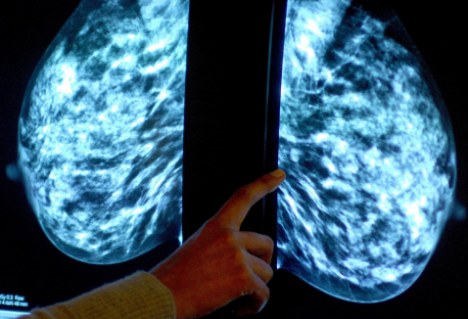

“原為尋找宇宙內(nèi)超新星而設計的技術,現(xiàn)在正被用于癌癥的診斷?!睋?jù)英國《每日郵報》網(wǎng)站3月10日報道,天文學家現(xiàn)與劍橋大學的腫瘤學家組成工作小組,將曾用來區(qū)分單個恒星和遙遠星系的電腦軟件用于檢測乳腺腫瘤的類別。

發(fā)表在《英國癌癥雜志》的一篇研究報告顯示,研究人員曾使用天文軟件來分析2000名乳腺癌患者的腫瘤情況。報告顯示,該軟件可作出與人類病理學家一樣準確的判斷,并在某些情況下,它得出的分析更加客觀。